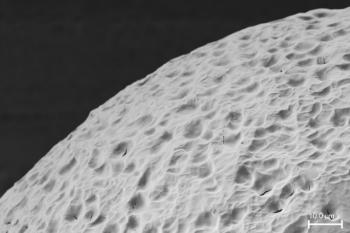

Image credit: Arturo J Vegas et al.

Il nuovo biomateriale è un derivato di alginato, un materiale originariamente isolato da alghe brune.

I ricercatori hanno scoperto che è possibile utilizzare gel di alginato per incapsulare le cellule pancreatiche. Il gel consente il passaggio delle molecole di glucosio nelle capsule in modo che le cellule pancreatiche sono in grado di rilevare e rispondere ai cambiamenti biologici.

Tuttavia, i ricercatori hanno scoperto che le superfici delle capsule impiantate nei primati e nell’uomo, alla fine si ricoprono di tessuto cicatriziale, impedendo il passaggio delle molecole e limitando l’efficacia di tutti i dispositivi incapsulati.

Cercando tra centinaia di derivati di alginato, i ricercatori hanno concentrato la loro attenzione sul triazolo-tiomorfolina biossido (TMTD) e lo hanno testato su topi diabetici con un sistema immunitario forte. Hanno impiantato le cellule insulari umane incapsulate in TMTD nella cavità addominale degli animali.

I ricercatori hanno anche testato il nuovo biomateriale – in forma di capsule vuote – impiantandole nella cavità addominale di primati non umani. Le capsule sono durate almeno 6 mesi senza accumulare tessuto cicatriziale.